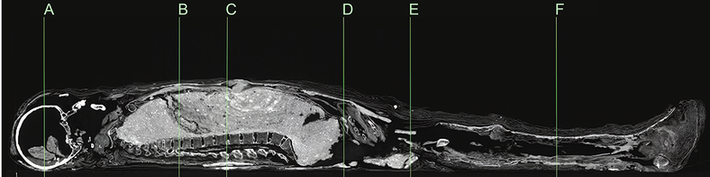

Gần đây, nhà khảo cổ Karin Sowada (Đại học Macquarie, Australia) dẫn đầu một nhóm chuyên gia có phát hiện lớn. Nhóm của ông phát hiện xác ướp được bọc bằng bùn trông như chiếc kén. Đây là điều rất hiếm gặp.

Sau khi qua đời, người phụ nữ được ướp xác và quấn nhiều lớp vải. Thi hài này đầu gối trái và cẳng chân bị phá hủy có thể là do những tên trộm mộ gây ra. Vì vậy, con cháu của người chết đã bọc lại xác ướp và trát bùn xung quanh.

Lần này, những người thợ dùng hỗn hợp phức tạp gồm bùn, cát và rơm giữa các lớp vải quấn bằng lanh. Lớp phủ nền có chất tạo màu từ calcite trắng trong khi lớp trên cùng phủ đất son, một loại khoáng chất màu đỏ.

Khi trát lên xác ướp, lớp bùn vẫn còn ẩm và dễ uốn nặn. Từ đó, xác ướp có hình dáng giống chiếc kén.